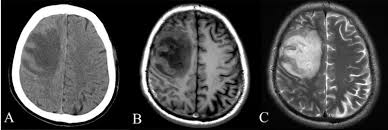

As you can see from the comparison image, a lesion which is very broad in the CT scan of A is much more defined in image C. Additionally, while the skull in A is very well defined, it is tough to determine where it is exactly in either B or C.

You might think, “why not just take the best image and use that?”. However, it is hard to decide which is the best image precisely for the reasons above. If only there was a way to get the best features from each image into a single “master image”. Well that is precisely what image registration is made for!